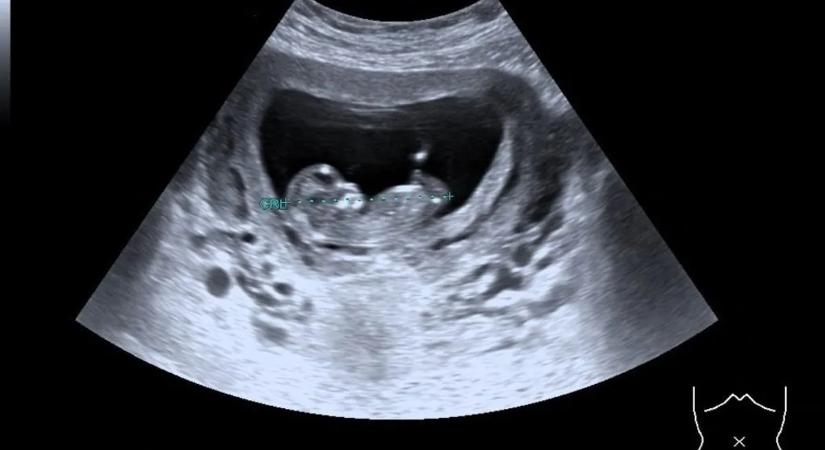

Csodabébi született a halott donorból átültetett méhből

Áttörés a reproduktív orvostudományban.